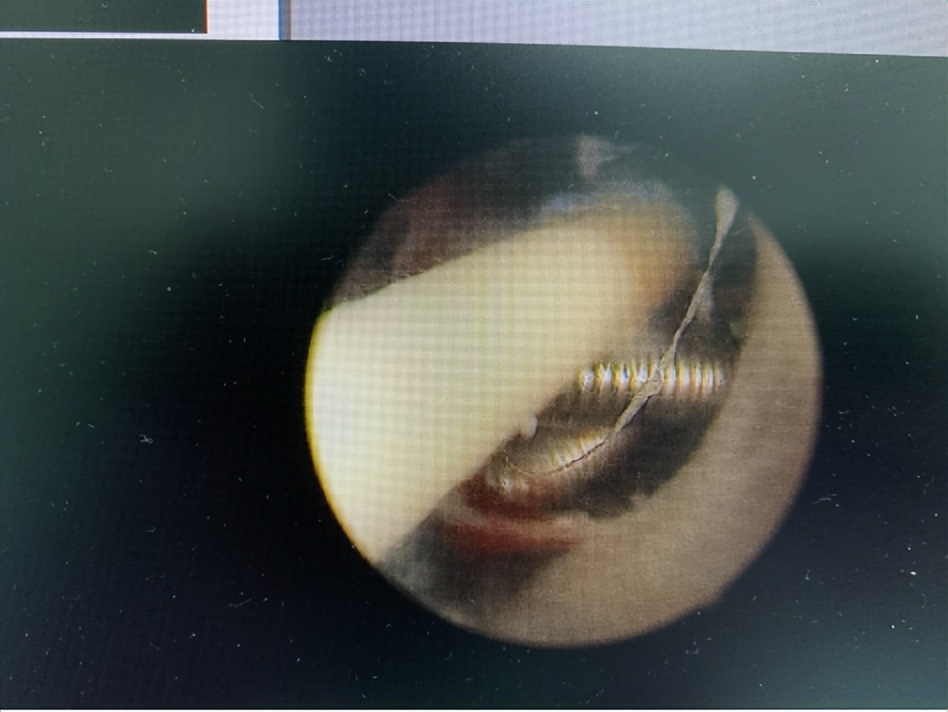

▶宫腔镜下取环术顺利取环

金阿姨来到广州中医药大学深圳医院,由毛东伟主任接诊。毛主任在详细询问金阿姨的病史后,决定为金阿姨做宫腔镜检查术,一探究竟。

毛主任立即召集科室医生进行术前讨论。因为金阿姨这个环戴了很多年,而且X线显示有可能有两个环,并且已经超过环的使用期限,环很可能崁顿子宫肌层。全体医生对术中可能出现的风险进行了激烈的讨论,并且针对术中可能出现的风险做了多项预备方案为确保手术顺利进行。

手术如期进行,术中医生克服重重困难,成功地取出宫内的节育器,一个T型环,一个圆环。金阿姨十分感谢妇科全体医护人员在术前、术后的诊疗和护理。

△宫腔镜下取环术术中